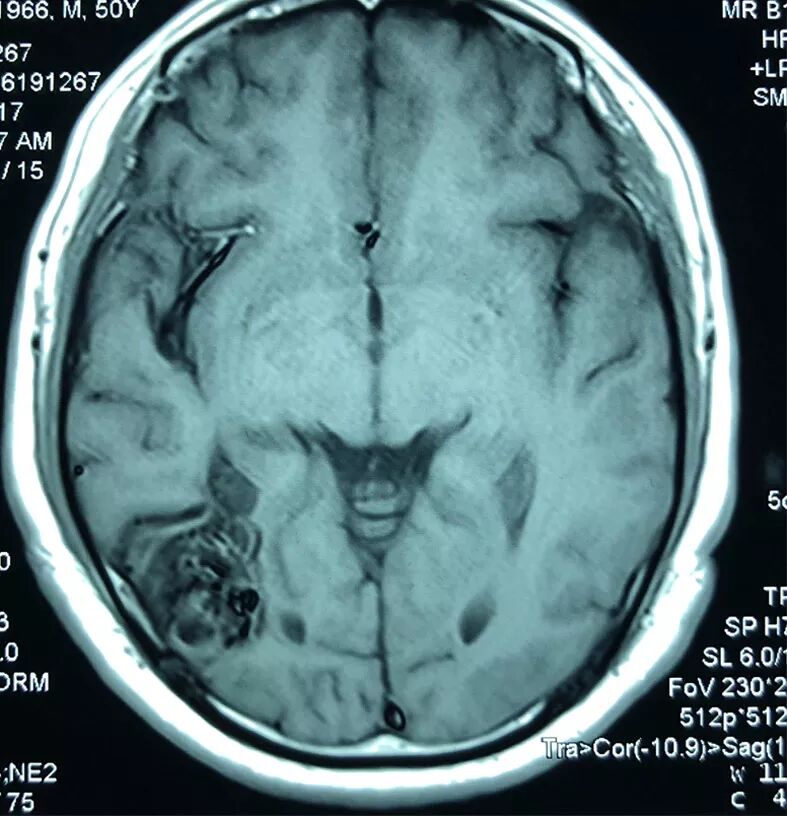

术前影像学检查

1. 磁共振考虑右侧枕叶血管畸形可能性大,建议DSA检查。

术后CTA见血管畸形切除完全,IIa动脉瘤夹闭完全